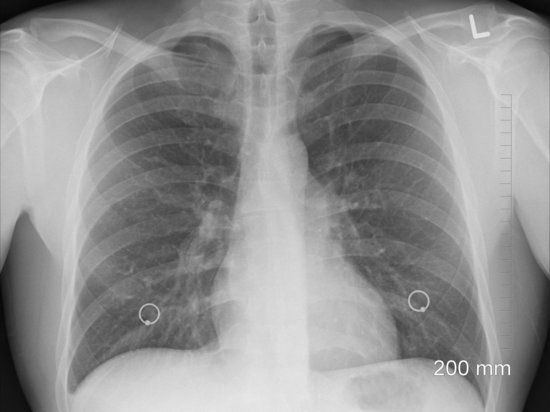

Иллюстрации и схемы восстановления легочной ткани